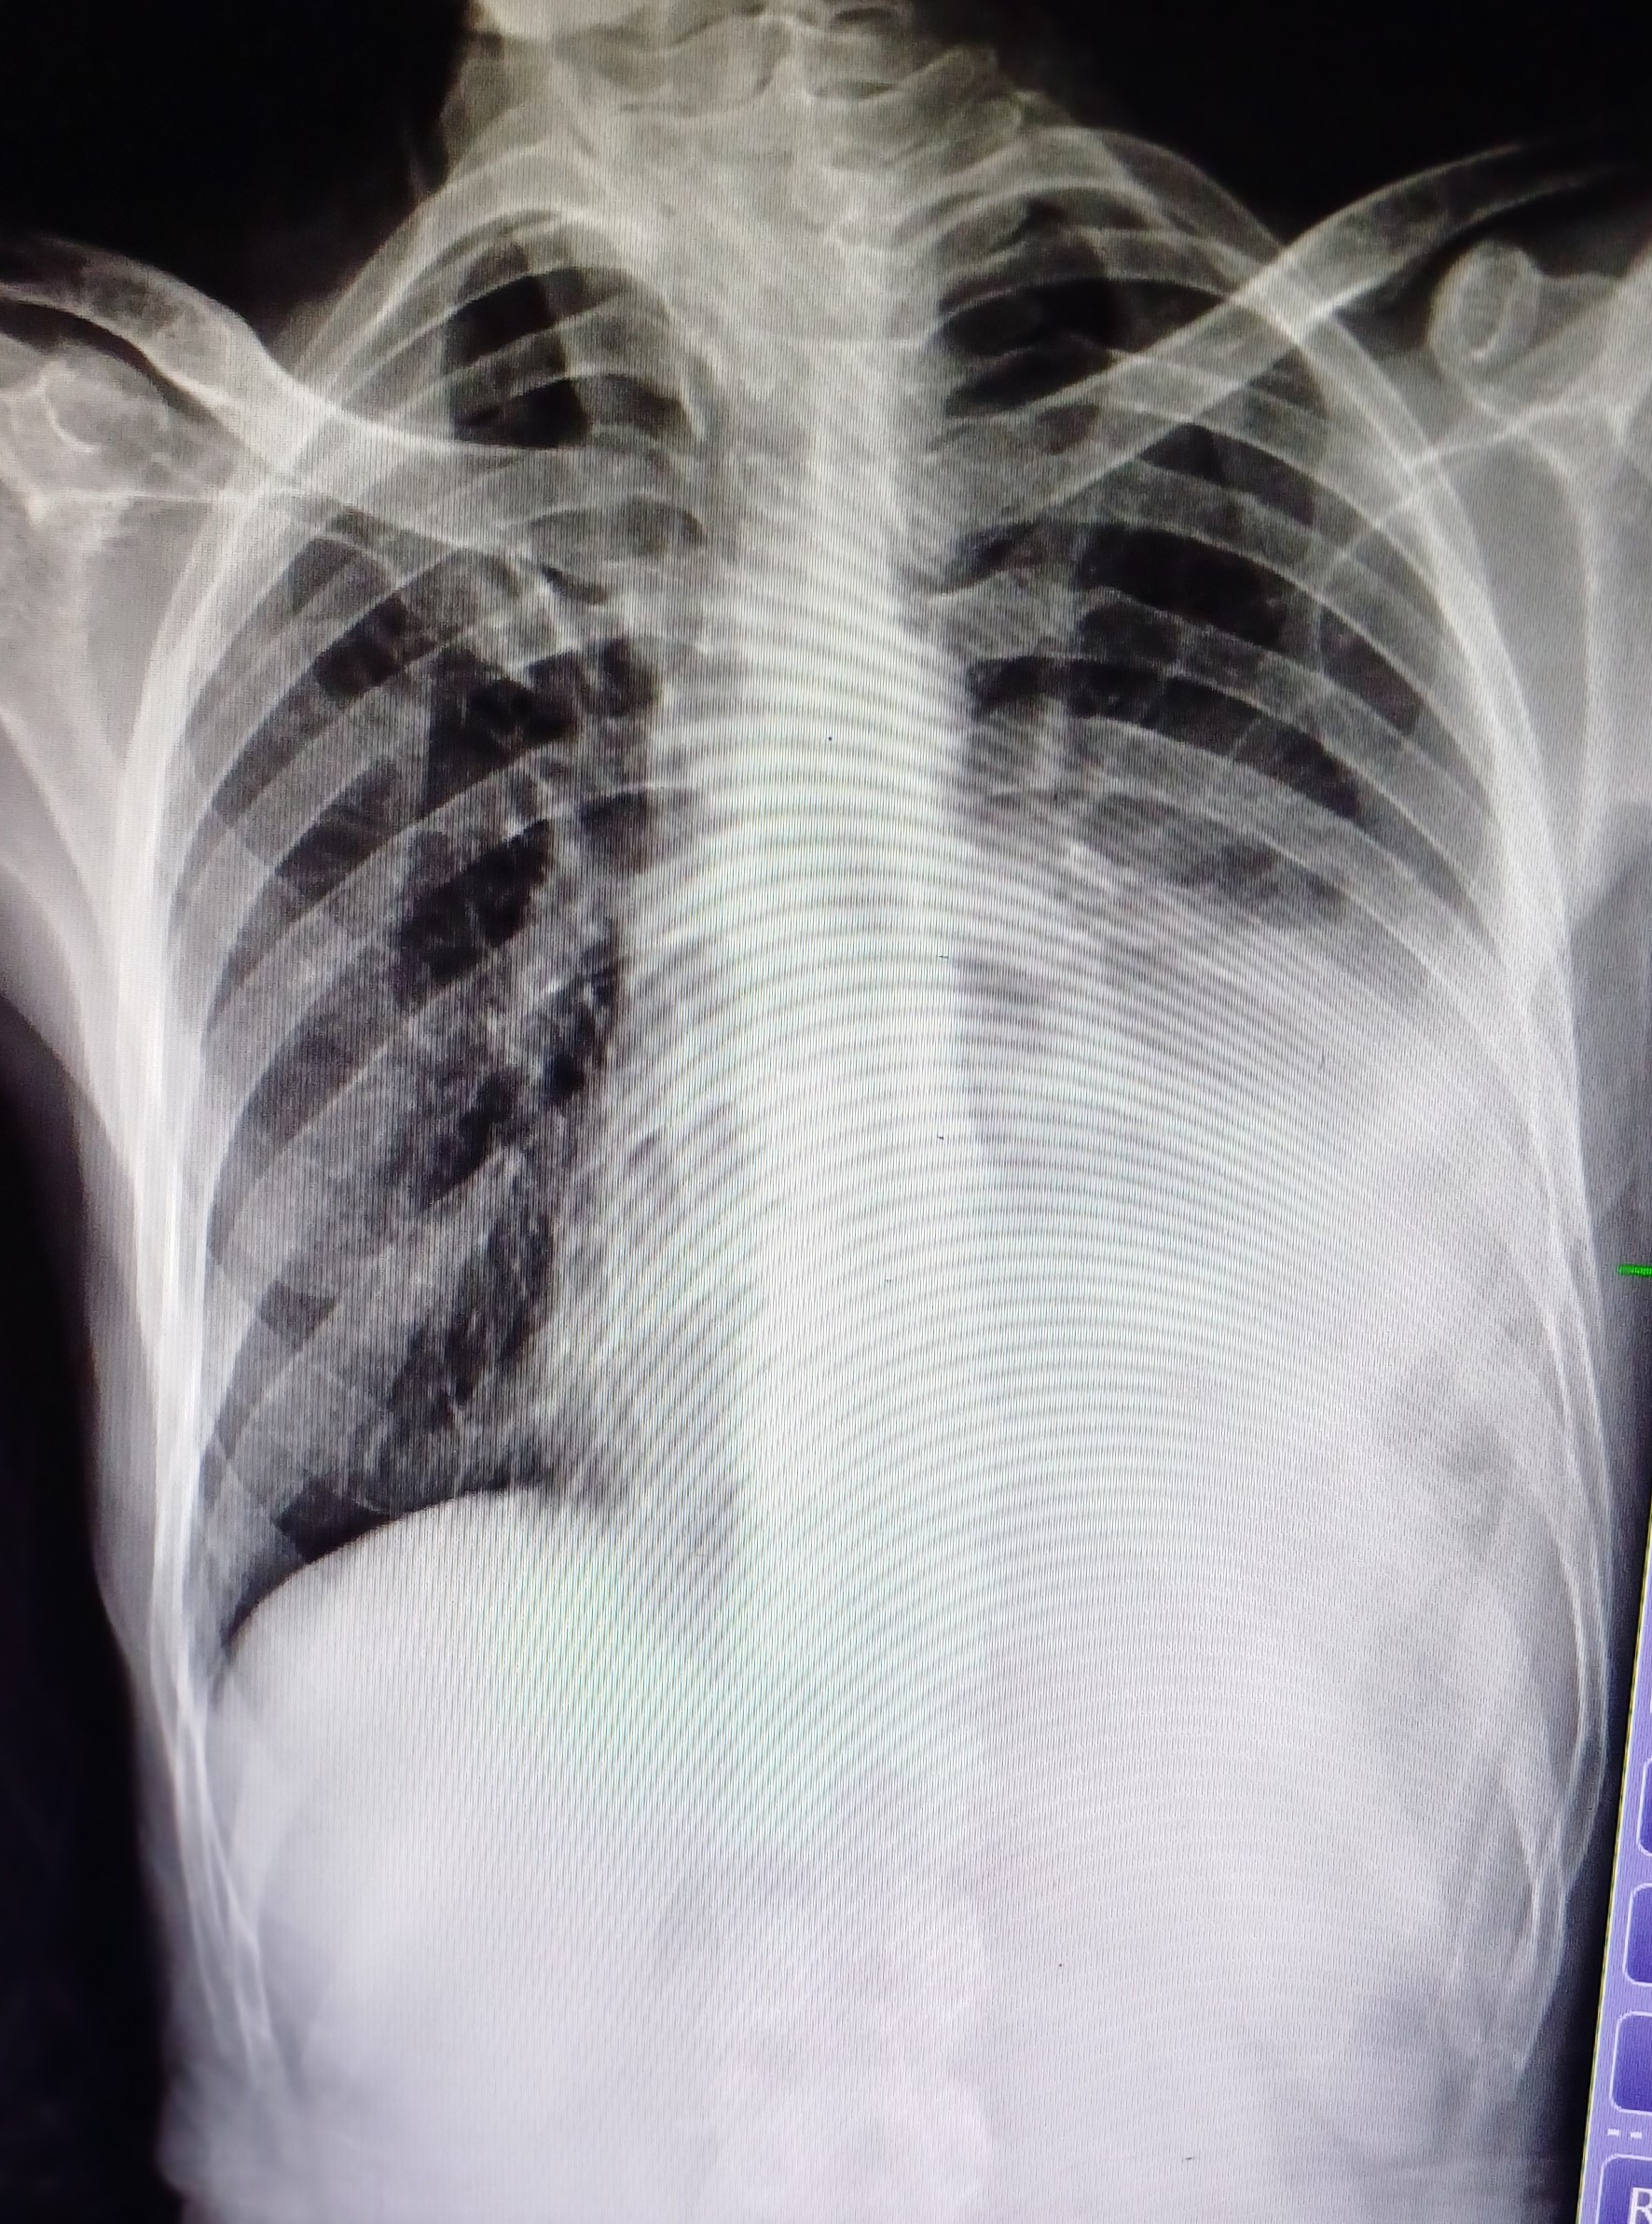

| 5 | IGGMC, Nagpur, Nagpur | P2 | 29-4467 | Meera Gohare | Consent taken on Paper | 64 Yrs. |

Provisional Diag : ?

Final Diag : Disseminated TB (Miliary TB With Abdomen Koch) |

TB Case (Confirmed) | Abnormality visible on x-ray |

View |

||||